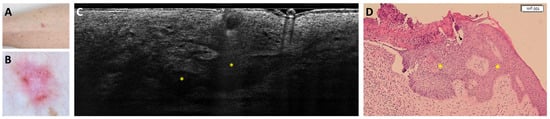

- Suppa, M.; Fontaine, M.; Dejonckheere, G.; Cinotti, E.; Yélamos, O.; Diet, G.; Tognetti, L.; Miyamoto, M.; Orte Cano, C.; Perez-Anker, J.; et al. Line-field confocal optical coherence tomography of basal cell carcinoma: A descriptive study. J. Eur. Acad. Dermatol. Venereol. 2021, 35, 1099–1110. [Google Scholar] [CrossRef]

- Ruini, C.; Schuh, S.; Gust, C.; Kendziora, B.; Frommherz, L.; French, L.E.; Hartmann, D.; Welzel, J.; Sattler, E. Line-field optical coherence tomography: In vivo diagnosis of basal cell carcinoma subtypes compared with histopathology. Clin. Exp. Dermatol. 2021, 46, 1471–1481. [Google Scholar] [CrossRef]

- Boussingault, L.; Lenoir, C.; Stefani, A.D.; Cappilli, S.; Fontaine, M.; Diet, G.; Miyamoto, M.; Cinotti, E.; Tognetti, L.; Pérez-Anker, J.; et al. Line-Field Confocal Optical Coherence Tomography of Basal Cell Carcinoma: Systematic Correlation with Histopathology. Diagnostics 2025, 15, 3059. [Google Scholar] [CrossRef] [PubMed]

- Donelli, C.; Suppa, M.; Tognetti, L.; Perrot, J.L.; Calabrese, L.; Pérez-Anker, J.; Malvehy, J.; Rubegni, P.; Cinotti, E. Line-Field Confocal Optical Coherence Tomography for the Diagnosis of Skin Carcinomas: Real-Life Data over Three Years. Curr. Oncol. 2023, 30, 8853–8864. [Google Scholar] [CrossRef]